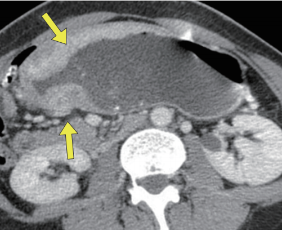

췌장은 소화 효소와 인슐린을 생산하는 장기로, 만약 이 장기에 문제가 생기면 심각한 건강 문제가 발생할 수 있습니다. 췌장염, 췌장암 등은 복부 CT를 통해 손쉽게 진단할 수 있으며, 췌장의 구조와 주변 조직 간의 상호작용을 명확히 확인할 수 있습니다. 특히 췌장암은 조기 발견이 매우 어렵지만, CT를 통해 미세한 종양까지 확인이 가능하므로 결과적으로 치료 효과를 극대화할 수 있습니다.

췌장염: 원인과 증상

췌장염은 췌장이 염증으로 인해 기능을 상실하는 질환으로, 주로 알코올 소비와 그에 따른 지방 간섭이 주요 원인으로 알려져 있습니다. 췌장염의 증상으로는 극심한 복통, 구역질 등이 있으며, 이러한 증상을 주의 깊게 살펴보는 것이 중요합니다. 복부 CT 검사는 즉각적인 진단을 통해 적절한 치료 계획을 세우도록 도와줍니다.